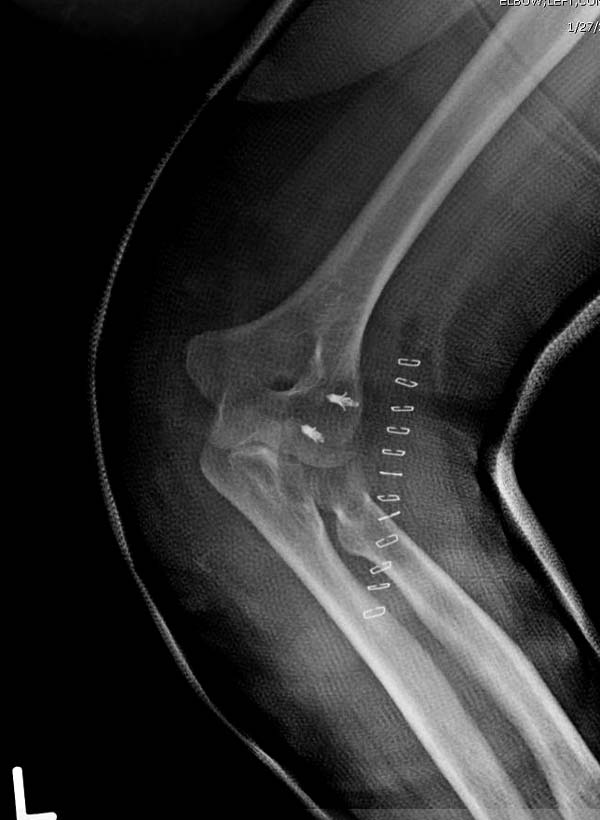

Снимки: 1-2 вывих, 4-5 вторичное смещение в гипсе, реконструкция

латеральной связки и капсулы 13-14, повторный вывих после реконструкции,

Имя     : 13 Elbow dislocation PO.jpg

Тип     : image/jpeg

Url     : http://weborto.net:8080/pipermail/ortho/attachments/20131212/4b05a6a3/attachment-0010.jpg